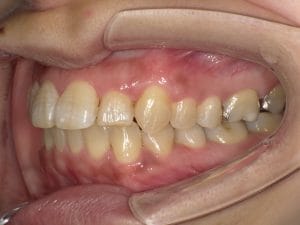

Case028 – セラミック矯正

歯並びと噛み合わせを治したいということを主訴に来院してくださった患者様の症例です。

前医の矯正専門医でマウスピースによる矯正では綺麗にならないといわれ、ワイヤー矯正はしたくなく、当院でセラミックで治したいということで来てくださいました。

初診時カウンセリングを含め計3回の診療、期間は三週間で前歯を内側に引っ込め、噛み合わせが交差咬合という不正咬合になってるところも治しました。

前歯が内側に引っ込むことで、口周りの軟組織もしまってお顔立ちもとても若々しくシュッとされ、より洗練されたイメージになりました。

当院はインビザラインによるマウスピース矯正、ワイヤー矯正、セラミック矯正の全ての矯正をやる事ができますが、その中で患者様のご希望、状態にあったもので、最善の治療をする事を心がけております。

担当 理事長 佐藤 悠野